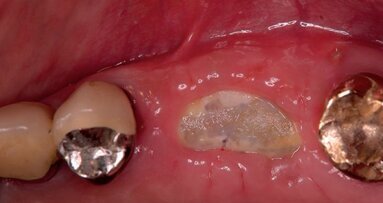

- Ripristinare un difetto osseo (Figg. 1-3).

- Preservazione del capitale tessutale (chirurgia pre-implantare anticipata) (Figg. 4-10).

- Altri interessi della DA (Figg. 11-15).